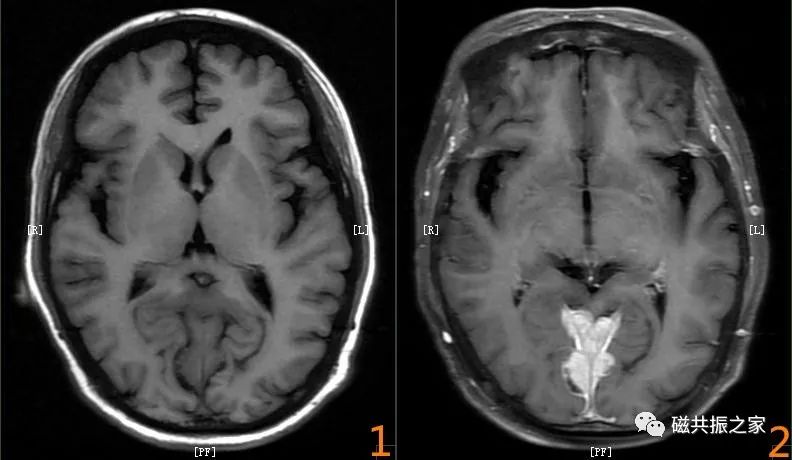

头颅mri入门系列之认识序列

图片尺寸960x769